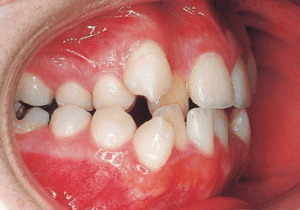

10 Perform lateral expansion of maxilla 7-4-’90 Midline is becoming deviated 9 years

11 During observation 4-1-’93 Midline deviation has become even greater 11 years 9 month

The Edgewise appliance was applied locally (8) and removed after 11 months (9). However, as the maxillary molar region gradually became crossbite, the maxillary arch was laterally expanded using a quad helix.

X-rays confirmed significant differences in the length and orientation of the mandibular ramus on the left and right sides. It was determined that orthodontic treatment alone would be insufficient, and a decision was made to proceed with treatment incorporating surgical intervention.